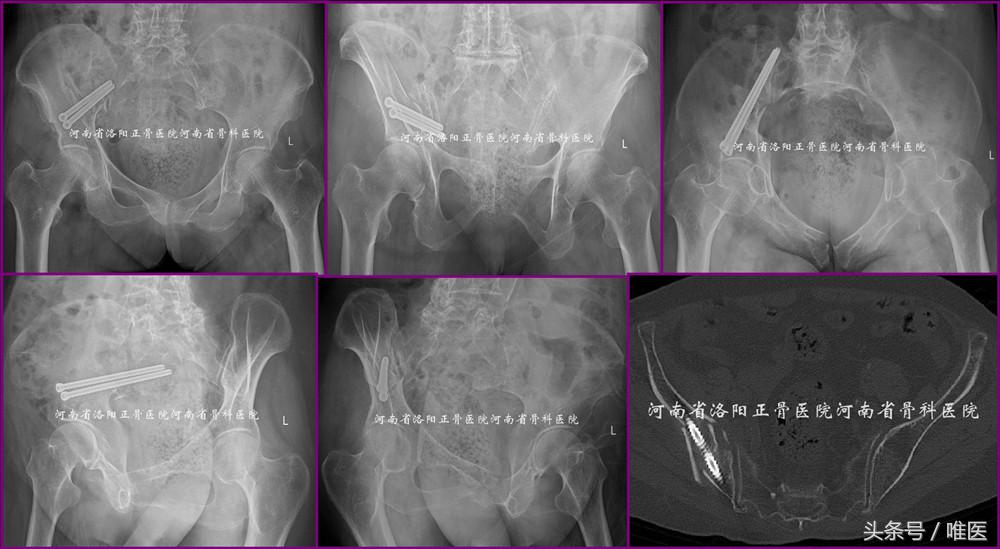

一例88岁女性病人因摔伤导致右半骨盆疼痛、右髋活动受限五天入院。其合并高血压病及心律失常。化验显示轻度贫血及低白蛋白,肝肾功能正常。彩超显示心脏功能正常,双下肢无静脉血栓形成。影像检查见图1。入院诊断:骨盆骨折(OTA-61B2.3):1.右侧髂骨新月形骨折;2.右侧耻骨上下支骨折。问:如何治疗?保守or手术?如手术,切开or闭合?每人都有自己的答案。但通过本期的讲解,相信大家会得出一个优选答案。

图1. 一例88岁女性骨盆骨折的影像资料。